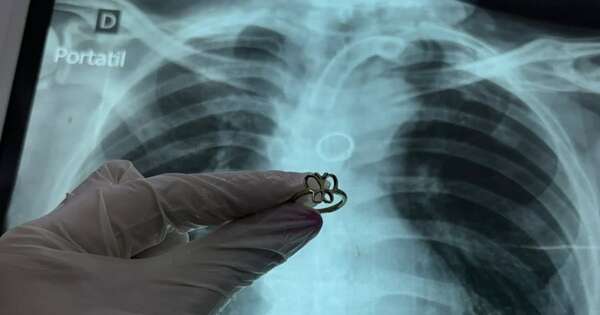

Un anillo de oro con forma de mariposa estaba alojado en el pulmón de un paciente con traqueotomía que fue a su control de rutina. Hasta el momento es un misterio para los familiares y médicos en qué circunstancias terminó el objeto terminó en su interior. ...[Leer más]